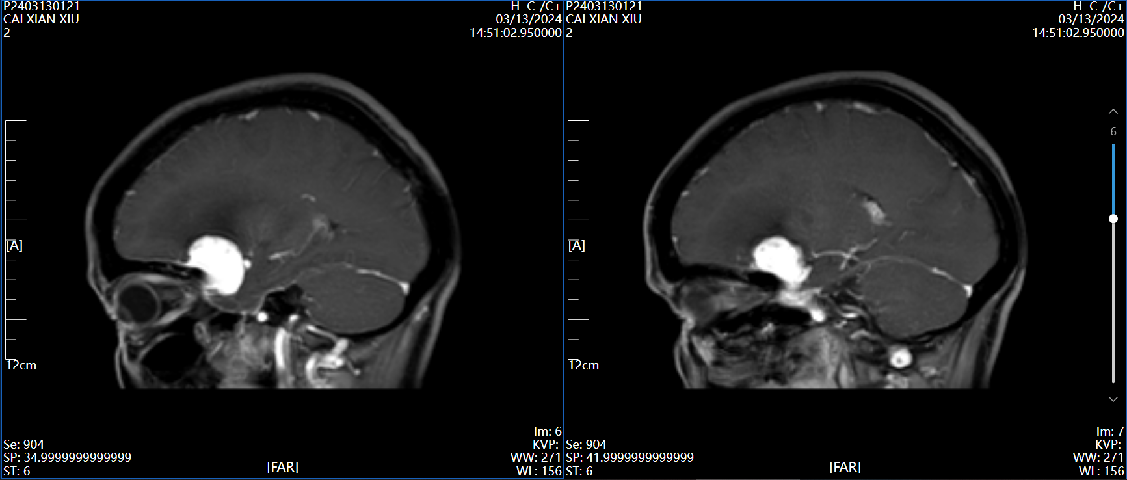

4、辅助检查:头颅磁共振检查提示:左侧前床突占位,约2.8×2.4×2.0cm大小,T1呈等低信号,T2呈等高信号,增强病灶明显强化,宽基底与前颅窝底、前床突相连,看见脑膜尾征。

磁共振 T1

磁共振T2